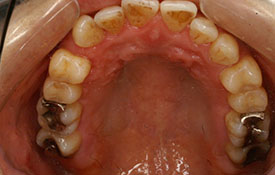

インビザラインの治療例:CASE-1

| プロフィール | 42歳 女性 |

| 所見 | 他院で行われた矯正歯科治療後の後戻りに悩まれて来院されました。 アイライナーの装着は、1日平均20時間ほどでした。 |